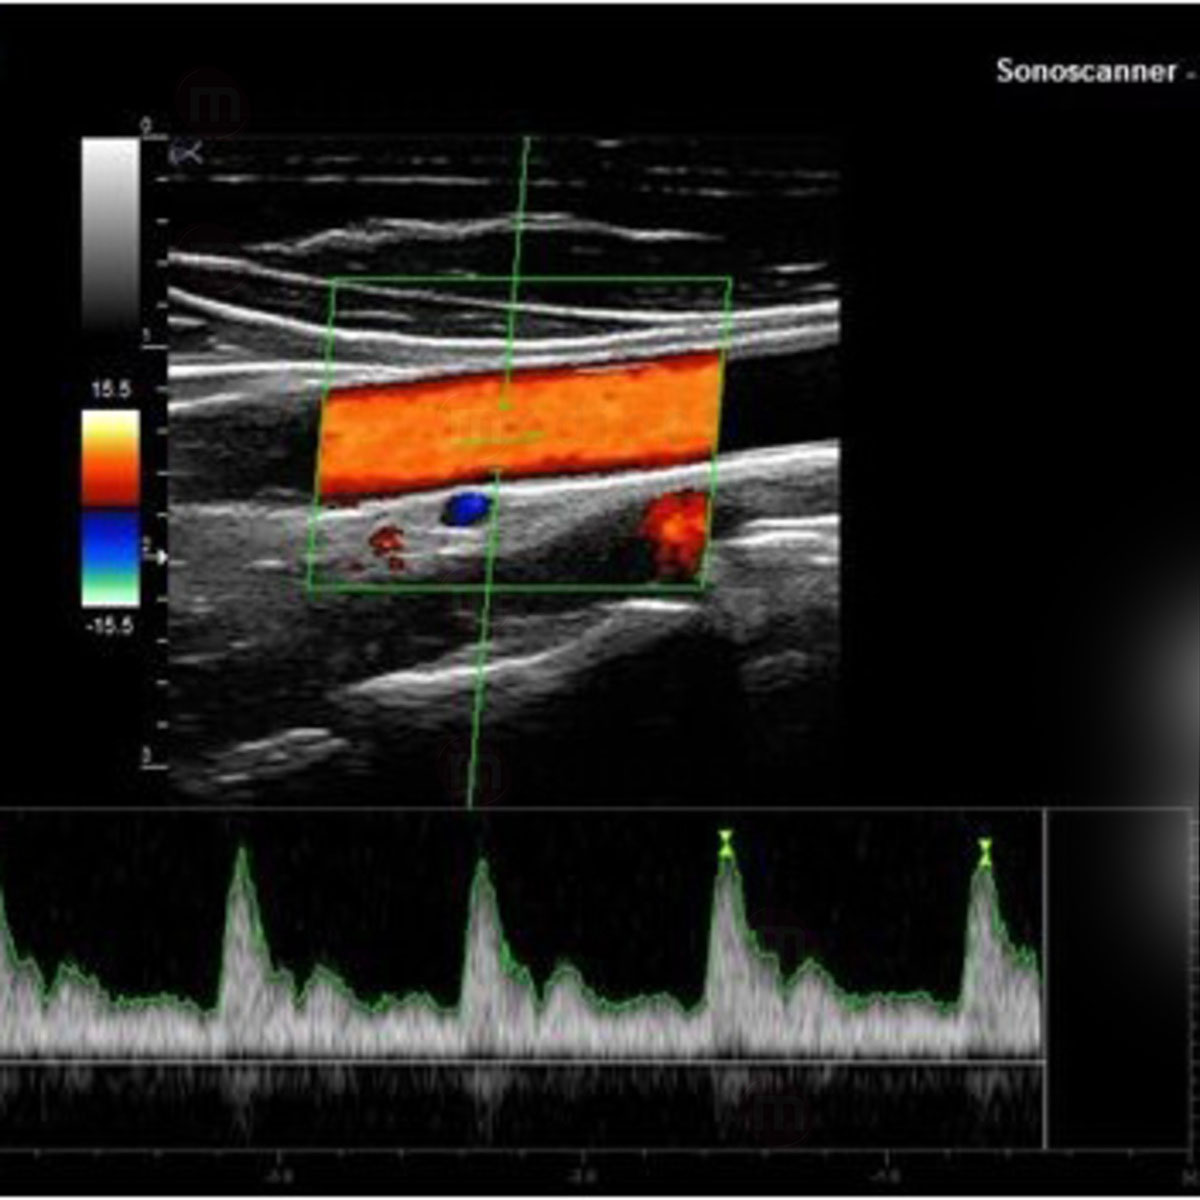

- Doppler Pulsé (PW)

- Doppler Couleur

- Doppler Energie

- Doppler Directionnel Energie

- Mode Duplex

- Mode Triplex

- Vasculaire

- Sonde Linéaire HD Très haute fréquence 8-18 MHz (Parties molles, Vasculaire, Anesthésie, MSK, Médecine du sport, Pédiatrie)

- Sonde linéaire 5-10 MHz (Parties molles, Vasculaire, Anesthésie)